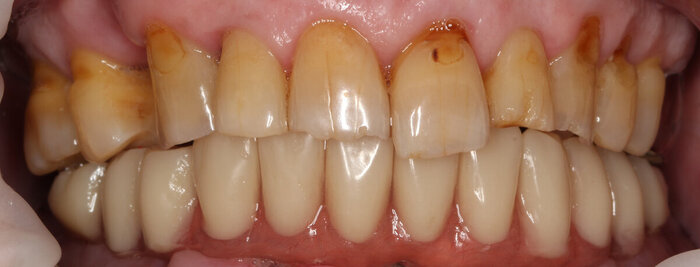

Посмотрим, что во рту:

Временный адаптационный протез с опорой на 6 имплантов. Нижняя челюсть.

До.

До имплантации.

А вот что стало после.

Верх пока не трогаем. Там останутся свои фронтальные зубы, нужно пройти через этап синус-лифтинга и прочее разное. Пока дадим пациенту восстановиться и отдохнуть.